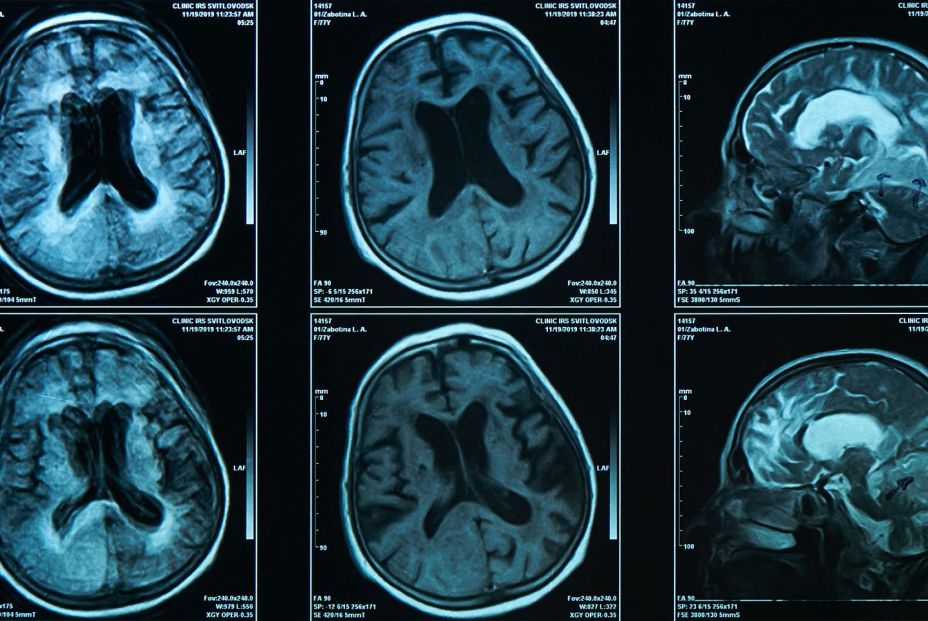

Los signos de mala salud cerebral se examinaron a través de imágenes de resonancia magnética de los cerebros de los participantes: hiperintensidades de la materia blanca, definidas como daños acumulados en la materia blanca del cerebro, que pueden afectar la memoria, el equilibrio y la movilidad; y daño microestructural, que es el grado en que la arquitectura fina del cerebro ha cambiado en comparación con las imágenes de un escáner cerebral normal de un adulto sano de edad similar.

Así, los expertos observaron que las personas genéticamente propensas a las caries, a las que les faltaban dientes o necesitaban dentaduras postizas tenían una mayor carga de enfermedad cerebrovascular silenciosa, representada por un aumento del 24 por ciento en la cantidad de hiperintensidades de la sustancia blanca visibles en las imágenes de resonancia magnética.